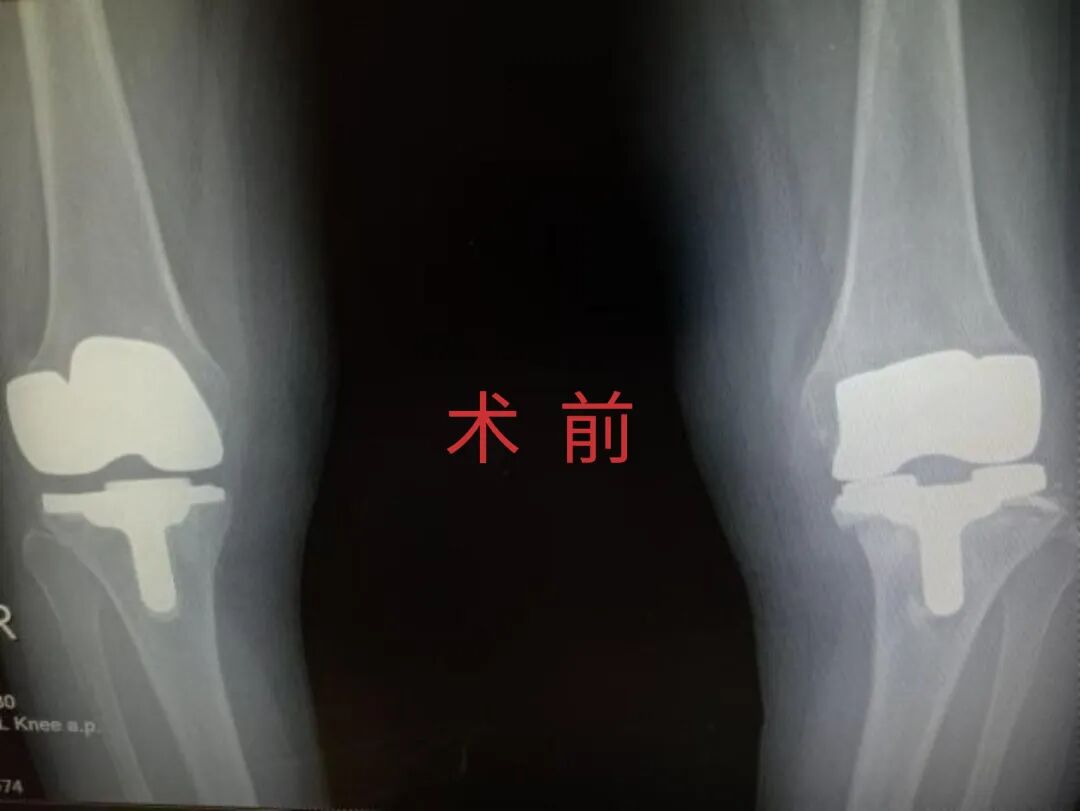

2025年11月1日,由遵义市医学会手外科分会主办、遵义市第二城市医疗集团(贵州航天医院)承办的遵义市医学会手外科分会学术交流会暨贵州省继续医学教育项目《急诊手外伤治疗临床研究新进展专题研讨班》在贵州航天医院成功举办,汇聚了遵义市手外科领域专家及基层医疗骨干,通过专题研讨与临床经验分享,共探急诊手外伤诊疗新进展。 会议特邀遵义市医学会手外科分会主任委员金文虎教授,遵义市医学会手外科分会副主任委员张子阳教授,遵义市医学会手外科分会常务委员杨绍浦教授,贵州航天医院陈明勇教授、赵兴东教授等遵义市手外伤专家进行交流分享;贵州航天医院党委委员、副院长彭亮参加会议并致辞,贵州航天医院骨科医务人员,遵义市第二城市医疗集团成员单位及红花岗区、绥阳县、桐梓县等区县医疗机构手外伤骨干参与。 贵州航天医院党委委员、副院长彭亮致辞 学术交流 本次学术交流以“急诊手外伤治疗临床研究新进展”为主题,通过理论授课与临床案例结合,共同探讨急诊手外伤临床诊疗全链条诊疗策略、关键技术、临床研究新进展,促进规范化诊疗技术向基层下沉,助力提升区域手外伤应急处置与修复能力。 贵州航天医院赵兴东教授分享《急诊手外伤的诊断与治疗原则》 贵州航天医院陈明勇教授分享《开放性骨折的治疗原则》 贵州航天医院张军教授分享《甲沟炎Winograd手术的临床应用》 贵州航天医院赵兴东教授分享《手部常见的皮肤缺损及治疗原则》 贵州航天医院张艳金教授分享《开放性骨折的清创术》 贵州航天医院冷家雄教授分享《下肢创面修复的常用皮瓣之股前外侧皮瓣》 贵州航天医院邬夏荣教授分享《踝关节慢性不稳的诊治》 贵州航天医院卢懿明教授分享《掌骨骨折》 贵州航天医院张艳金教授分享《手部肌腱的解剖与修复方法》 本次研讨班为遵义市手外科领域医务人员提供了深度交流契机,强化了医疗机构间的协作网络,进一步推动学科创新与临床实践融合,为健康遵义建设注入新动能。 贵州航天医院骨科专家简介 陈明勇 骨一科主任,副主任医师 临床擅长:从事创伤骨科工作约20年,对骨缺损、骨不连、骨肿瘤、肢体畸形等的肢体矫形重建及功能重建,慢性化脓性骨髓炎的根治治疗、糖尿病足的保肢治疗、快速康复理念(ERAS)下的老年骨折的诊治,四肢复杂骨折的诊治,四肢骨折等微创手术治疗具有丰富的临床经验。 2004年毕业于遵义医学院临床专业,曾在中国人民解放军总医院、广西医科大学第一附属医院、上海第六人民医院骨科进修。中国中西医结合学会骨伤科专业委员会横向骨搬移治疗糖尿病足及微血管网再生学组首届委员,遵义市医学会创伤分会常务委员。 瞿 晖 骨科党支部书记,骨二科主任,副主任医师 临床擅长:对骨科的常见病、关节外科、脊柱外科及运动医学疾病的诊治具有丰富的临床经验,熟练掌握骨科手术操作技术。 毕业于遵义医学院临床医学系,2005年前往广州中山大学第一附院骨显微医学部进修学习,2011年前往成都华西医院进修学习,并多次在省内外学习骨科相关知识,是中华医学会骨科分会会员。 赵小锋 中共党员,骨二科副主任,副主任医师 临床擅长:从事骨科临床工作11年,对骨科常见病、多发病诊疗有较为丰富的临床经验,擅长脊柱相关疾病诊断及治疗,尤其是颈、腰、腿疼痛疾病诊断及治疗,擅长胸腰椎骨折微创经皮穿刺内固定术、经皮穿刺椎体成形术、经皮穿刺脊柱内镜下腰椎间盘摘除术、单纯开创腰椎间盘摘除术、腰椎滑脱复位椎间植骨椎融合内固定术、腰椎管狭窄减压融合内固定术及人工髋、膝关节置换术等。 2012年毕业于遵义医学院外科学专业硕士研究生,2019年参加“遵义市115医学人才精英计划”于上海交通大学第一附属医院培训学习,2023年于北京大学第三人民医院脊柱外科进修学习,曾获得遵义市优秀医师荣誉称号。 遵义市手外科第一届委员,遵义市医学会创伤分会第一届委员,遵义市医学会创伤分会第二届委员,贵州省康复医学会第三届脊柱脊髓专业会委员,遵义市医学会烧伤与整形外科学分会委员,发表论文5篇,其中国家级核心期刊1篇,SCI论文1篇,主持市级课题1项并结题,参与市级课题2项。 赵兴东 骨科主任医师 临床擅长:擅长骨科的常见病及各种创伤、四肢骨折创伤修复、骨感染、手足疾病的诊治和手足体表畸形的矫形整复,熟练掌握骨科四肢骨病及创伤的手术操作技术,尤其在四肢关节复杂性损伤、手足外伤、组织缺损创面、难治创面的皮瓣修复方面及平足、高弓足矫形方面及四肢慢性疼痛诊治、康复方面具有丰富的临床经验。 硕士研究生,毕业于遵义医学院临床外科系,2015年前往山东省立医院手足外科进修学习;遵义市医学分会创伤分会第一、二届委员,遵义市手外科医学会第二委届员会常务委员;在省级及省级以上期刊发表文章9篇,参编著作2部,参与主持并完成市级课题1项,参与市级课题2项、省级课题1项。 张艳金 中共党员,骨科副主任医师 临床擅长:从事骨外科工作16年,对复合伤、多发伤的救治、四肢骨干骨折、关节周围骨折、骨肿瘤、骨髓炎等诊治具有丰富的临床经验。 中共党员,硕士研究生,2006年本科毕业于山西医科大学第二临床医学院,2011年研究生毕业于北京军区总医院;在“老年COPD患者合并髋部骨折的诊治”国际合作课题组研究两年,在老年髋部骨折的诊治方面具有丰富的经验,并发表论文6篇;主持遵义市级课题1项,承担遵义医科大学的临床教学工作,获得遵义医科大学优秀带教老师荣誉。编撰有《骨科疾病诊疗精粹》一书,开展2项新技术,编撰地方规范《务川自治县创伤骨科常见疾病诊疗规范》一书。 张俊凯 骨科副主任医师 临床擅长:从事骨科临床工作28年,对创伤骨折、骨感染、骨缺损、骨不连等外科诊治,四肢骨折的微创手术治疗,四肢复杂骨折(如关节内粉碎性骨折、多发骨折等)的损伤控制及手术治疗等具有丰富的临床经验。 1995年毕业于遵义医学院临床专业,2009年前往复旦大学附属医院骨科进修1年。 卢懿明 中共党员,骨科副主任医师 临床擅长:从事骨科工作18年,对创伤骨折、四肢骨折的微创手术治疗、四肢复杂骨折(如关节内粉碎性骨折、多发骨折等)的损伤控制及手术治疗,尤其是髋部骨折的PFNA等微创技术,踝关节骨折、膝关节周围骨折的Mipo微创技术等具有丰富的临床经验,开展了4项新技术,发明6项新型专利技术。 2005年毕业于遵义医学院临床专业,2017年,前往南方医科大学第三附属医院骨科进修半年,回院后运用Mipo技术对骨干骨折及干骺端骨折的治疗技术,同时积极开展骨盆骨折、髋臼骨折腹直肌外侧切口的应用;发表了多篇专业论文,经常参与省内外学术交流会授课,获得医院荣誉称号多个。 邬夏荣 骨科副主任医师 临床擅长:从事骨科工作16年,对四肢复杂骨折、骨肿瘤的诊治,尤其是足踝创伤、慢性踝关节损伤、平足症等诊疗具有丰富的临床经验。 2006年毕业于遵义医科大学临床医学专业,曾在陆军军医大学西南医院进修学习,发表多篇骨科学术论文。 余德怀 中共党员,骨科副主任医师 临床擅长:从事骨科工作10余年,对运动医学、骨关节、脊柱外科常见病、多发病的诊治具有丰富的临床经验。 硕士研究生,2011年毕业于遵义医学院临床医学专业,曾前往遵义医科大学附属医院运动医学专业进修学习;是贵州省医学会运动医学分会青年委员,西部关节镜联盟委员;发表多篇骨科学术论文。 冯 乾 骨科副主任医师 临床擅长:从事骨科工作近20年,熟练掌握骨科多发病及常见病的诊治,尤其对脊柱退变性疾病的诊断及治疗具有丰富的临床经验,主要研究脊柱微创相关治疗方式,能熟练开展椎间孔镜及UBE。 曾前往北京大学第三医院进修学习疼痛及椎间孔镜、首都医科大学友谊医院专业进修脊柱内镜;是贵州省康复医学会第三届脊柱脊髓专业委员会委员;发明专利3项、发表脊柱外科专业论文多篇。 贵州航天医院骨科简介 基本情况 贵州航天医院(原3417医院)骨科组建于1968年,前身是以创伤和断肢(断指)再植闻名于世的上海市第六人民医院骨科,中国断肢(断指)再植的奠基者、中科院院士陈仲伟等专家莅临科室指导医疗和教学,并在70年代开展了贵州省首例断肢(断指)再植手术。组建50余年来,诊治患者已逾百万,挽救了无数的伤病员,成为了保障遵义地区人民群众健康的重要支撑。 经过几代人的不懈努力,今天的骨科,已由创伤骨科发展至骨病、骨肿瘤、骨结核等领域,现有脊柱外科、关节外科、四肢创伤、手足外科四个亚专科,成为了集医疗、教学、科研于一体的综合学科,是贵州省临床重点专科、遵义市临床重点专科、遵义市骨科临床医学中心、遵义市基层骨科专科联盟理事长单位。 科室目前开放床位110张,共有医护人员50余人,副高级以上专家18人,硕士研究生15人。拥有一流骨科医疗设备多台,每年不定期选派优秀技术骨干到全国各大知名医学院校进修、学习、参观、交流,并邀请国内、国外知名专家教授来院进行交流、指导,通过不断引进国内外先进的诊疗技术,科室医疗技术水平稳步提升,为广大人民群众提供了优质的医疗服务。 专科特色 骨一科 (一)骨缺损、骨不连的肢体与功能重建 胫骨横向骨搬移技术治疗糖尿病足: (二)慢性骨髓炎的根治治疗 (三)肢体缺血性疾病如糖尿病足、脉管炎的保肢治疗 (四)皮瓣修复 (五)复杂创伤的治疗 (六)老年髋部骨折及小儿骨折快速手术 老年髋部骨折: 骨二科 (一)胸腰椎骨折微创经皮椎弓根螺钉固定术 (二)老年性骨质疏松性患者腰椎滑脱脊柱内固定术(骨水泥螺钉) (三)V形双通道脊柱内镜技术(VBE)腰椎融合术治疗腰椎退行性疾病 (四)老年性骨质疏松性骨折(PVP/PKP)术 (五)人工髋关节置换术 (六)双侧股骨头坏死人工全髋关节置换 (七)右侧全髋置换术后假体周围骨折翻修 (八)人工膝关节置换术 (九)人工膝关节假体松动翻修 (十)关节镜技术 传统手术切口 关节镜技术切口 诊疗范围 骨一科 1.四肢创伤、矫形。 2.手、足踝外科。 骨二科 End